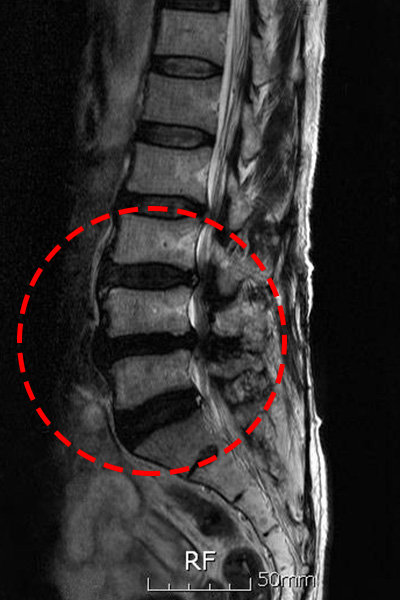

척추관 협착증 치료 방법

척추관 협착증 환자는 협착된 척추관 부근에 염증이 발생하여 심각한 통증을 느끼게 되고, 두꺼워진 인대가 신경을 압박하게 되고요. 자생한방병원에서는 염증과 부기를 가라앉히는데 효과가 있는 디스크 치료 한약으로 협착으로 인해 유발된 통증을 감량시켜주며, 부서진 근처 연조직의 흠집를 낫게 하죠. 한약은 퇴행된 뼈의 재생을 증대시키고 두꺼워진 인대 근처의 염증을 가라앉히는 효과가 있어요. 자생에서는 이런 한약과 나란히 척추관을 벌려주는 추나요법 등을 같이 진행하여 척추관 협착증을 치료하죠.

척추관 협착증이 진행하여 척수 손상의 증상이 나타나게 되면 다리의 경미한 운동마비, 건 반사 항진, 바빈스키 징조 등을 보이죠. 또한 감각장애로 통각, 운동감각 장애, 위치 진동감각 장애가 나타난다고 하고 신경인성 방광에 의한 배뇨 장애도 발생할 수 있어요. 수술 후, 통증 등은 호전을 보일 수 있겠지만 마비 등 일부 증상은 남을 수도 있어요.

척추관 협착증은 허리 부위에서 신경 압박으로 인한 통증과 기능 저하를 초래할능한 질환입니다. 비수술적 치료법을 시도한 후에도 효과가 없는 경우 수술적 치료를 계산해야 하고요. 또한, 적절한 운동은 척추관 협착증의 치료와 예방에 도와줄수 있습니다. 그러나 운동을 시작하기 전에 의사나 전문가와 의논하여 적절한 운동 강령을 구축하는는 것이 중요해요.